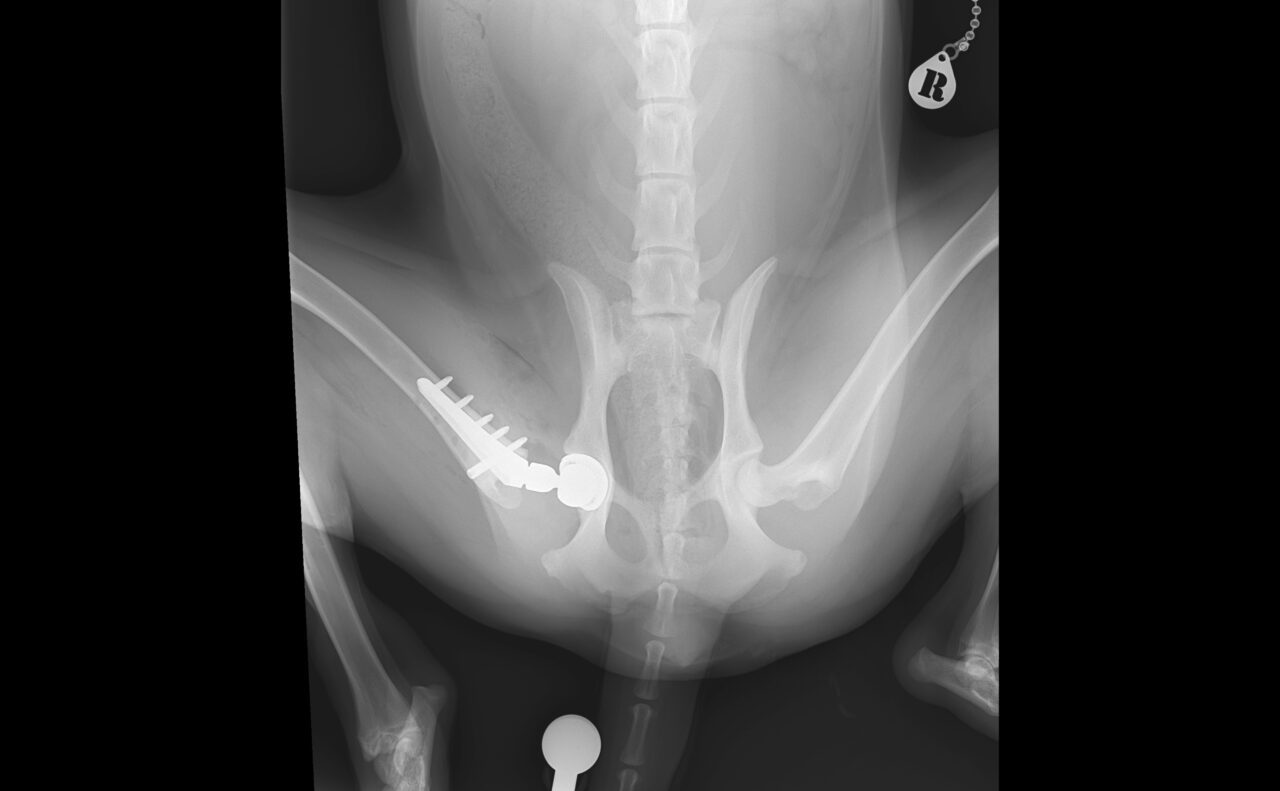

術後X線評価ではインプラント設置は良好。

カップは寛骨臼内側壁に適切に接触し、前後柱間で良好に中心化されています。

ステムは髄腔中央に位置し、内側皮質との接触も良好です。インターロッキングスクリュー固定も適切で、安定した初期固定強度が得られています。

Angle of Lateral Opening (ALO):約45°

Retroversion:約30°

True stem anteversion:約25°